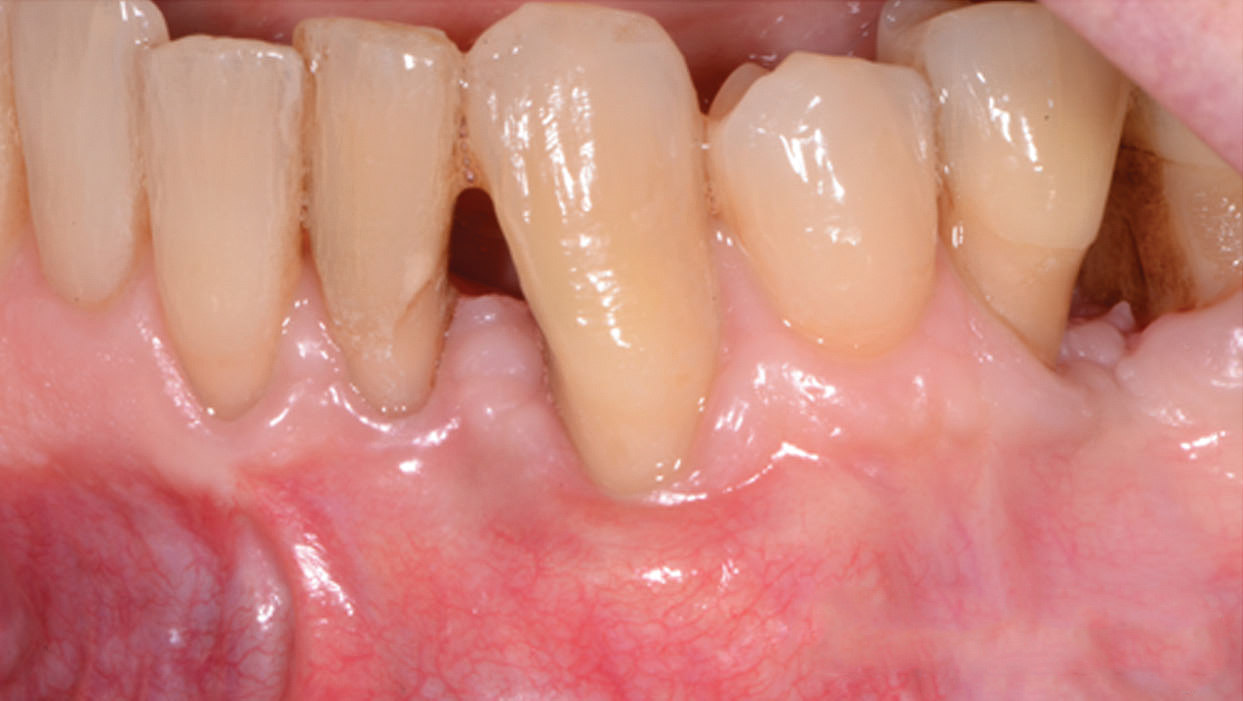

Synthetic polymers such as polycaprolactone (PCL) and poly-L-lactic acid (PLA) can be combined with natural polymers such as hydroxyapatite and β-tricalcium phosphate to allow the formation of biphasic constructs with tailored mechanical properties and rates of degradation. Recently, a first-in-human case report of a custom-designed, 3D-printed PCL scaffold for the treatment of a large periodontal defect was reported in combination with PDGF administration (Figure 3 through Figure 20).23 The scaffold was fabricated using selective laser sintering, which allowed for material powder to be fused together to form a structure based on a CAD file of the scaffold that was designed from CBCT scans of the patient defect. This novel approach offers a promising future application of 3D printing for customized scaffold designs that can be tailored to meet patient-specific needs based on defect site and location, with the added ability to deliver growth factors.

Fig 3. A 3D printed scaffold was designed using CAD software to fit a peri-osseous defect in a human patient. The scaffold consisted of a region with channels designed to support oriented PDL tissue formation and a region for the regeneration of osseous tissue. Fig 3: baseline;

Fig 4: defect model; Fig 5 through Fig 7: internal, tilted, and side views of scaffold, respectively; Fig 8 through Fig 10: coronal, middle, and apical

angles, respectively; Fig 11: cross-section diagram; Fig 12: labial scan image. (Images reprinted with permission from Rasperini G, Pilipchuk SP, Flanagan CL, et al. J Dent Res. 2015;94[9 suppl]:153S-157S.)

Figure 3